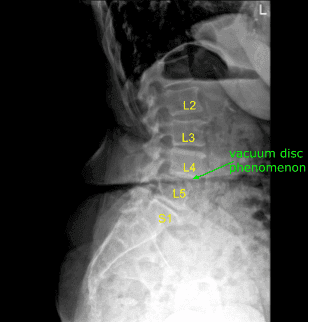

A patient presented to a neurosurgery clinic with signs and symptoms of lumbar stenosis with neurogenic claudication and a right-sided foot drop. Imaging showed severe stenosis at L4-5 centrally and L5-S1 on the left. Surgery was recommended to decompress her lumbar spine.

They were positioned prone on a Wilson frame. All Pressure points were carefully padded. Lumbar area was cleaned with chlorhexidine. A 22-gauge spinal needle and fluoroscopy was used to localize the L4-5 level.

We took a final x-ray confirming decompression of the foramina with a Woodson and a Penfield #4 in the L4-5 and L5-S1 foramina on the left side. The wound was irrigated copiously.Hemostasis was confirmed.